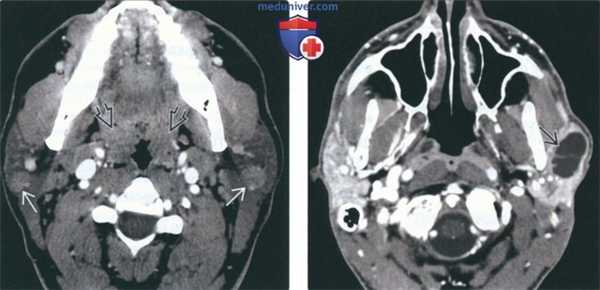

(Слева) КТ с КУ, аксиальная проекция. В обеих околоушных железах визуализируются солидные образования с четкими контурами. И хотя метастазы и лимфома могут выглядеть точно так же, гипертрофия небных миндалин позволяет заподозрить лимфоэпителиальное поражение или хроническую лимфаденопатию околоушных лимфоузлов при ВИЧ.

(Справа) КТ с КУ, единичная киста в левой околоушной железе, разделенная внутренней перегородкой. И хотя при доброкачественном лимфоэпителиальном поражении обычно обнаруживается сразу несколько образований, иногда они могут быть и единичными. В такой ситуации может быть выставлен неверный диагноз - киста первой жаберной щели.

(Слева) КТ с КУ, аксиальная проекция у пациента с объемным образованием шеи слева. Плотность обеих околоушных желез увеличена, в правой железе определяется многокамерная киста, в левой - смешанное кистозно-солидное образование.

(Справа) КТ с КУ, аксиальная проекция, этот же пациент. Определяется единичный увеличенный околоушной узел слева и гипертрофия небных миндалин. По результатам КТ пациенту было рекомендовано обследование на ВИЧ, результат оказался положительным.